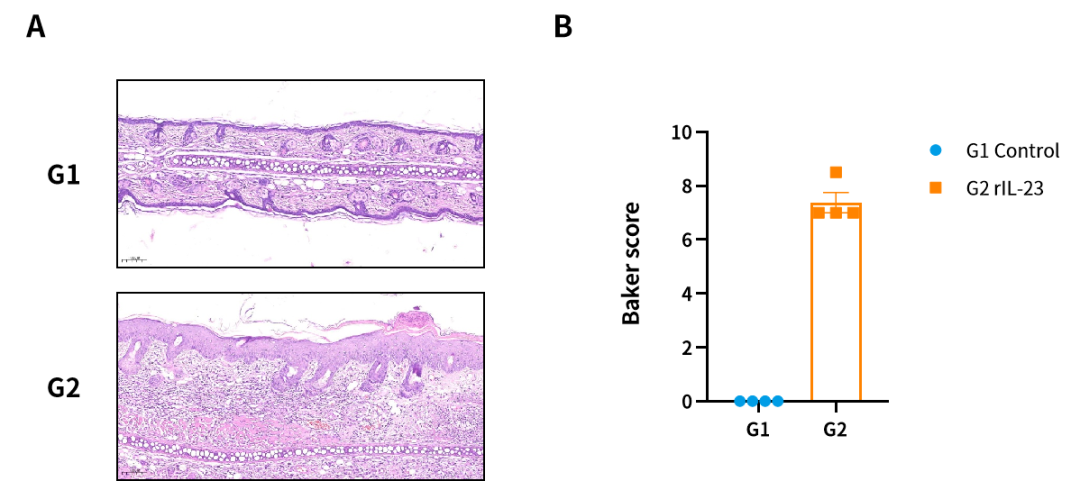

图4. Rat IL-23因子诱导的大鼠银屑病模型。(A)H&E染色代表图;(B)Baker评分。